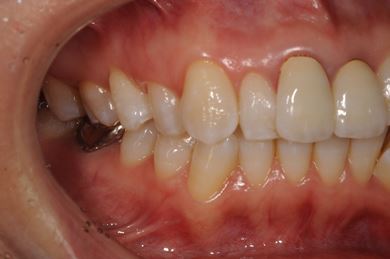

インプラント治療+セラミック治療

| 性別/年齢 | 女性 / 42歳 | ||||||||||||||||||||||||||||||||

| 主訴 | 別の病院で、右奥歯の根の部分にインプラント治療が必要と言われたので、セカンドオピニオンを希望。 | ||||||||||||||||||||||||||||||||

| 治療方針 | 右下奥、保存不能の歯を抜歯し、インプラント治療にて、機能的・審美的回復を行う。 | ||||||||||||||||||||||||||||||||

| 治療内容 | インプラント1本、メタルボンドセラミッククラウン2本(メタルボンド用土台1本) | ||||||||||||||||||||||||||||||||

| 総治療費 | 502,740円 | ||||||||||||||||||||||||||||||||

| 治療期間 | 1年3ヶ月 |